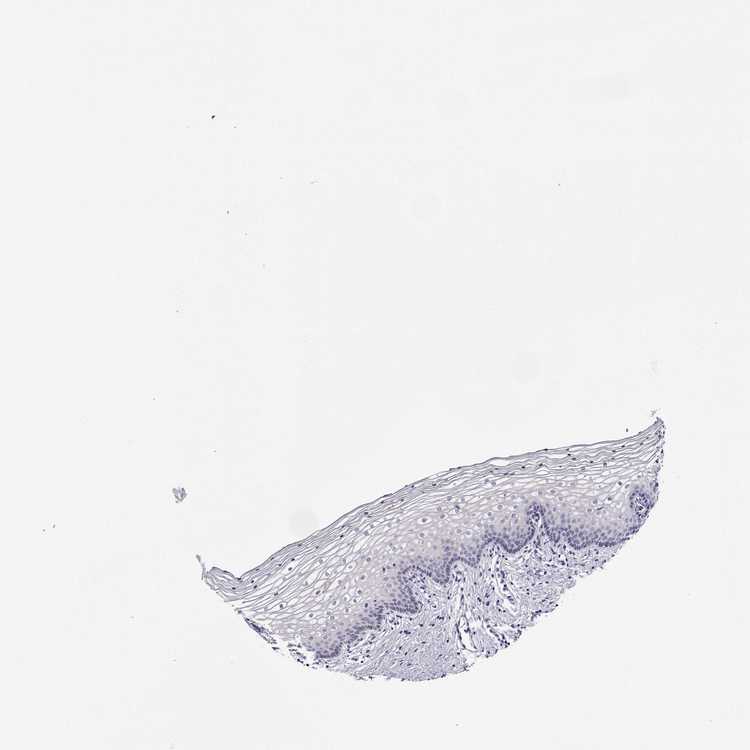

TISSUE PRIMARY DATA VAGINA Show tissue menu

VAGINA - Antibody stainingi

Antibody staining in the annotated cell types in the current human tissue is reported as not detected, low, medium, or high, based on conventional immunohistochemistry profiling in selected tissues. This score is based on the combination of the staining intensity and fraction of stained cells.

Each image is clickable and will lead to virtual microscopy that enables deeper exploration of all samples and also displays staining intensity scores, fraction scores and subcellular localization as well as patient and tissue information for each sample.

Antibody HPA078302

Squamous epithelial cells Not detected